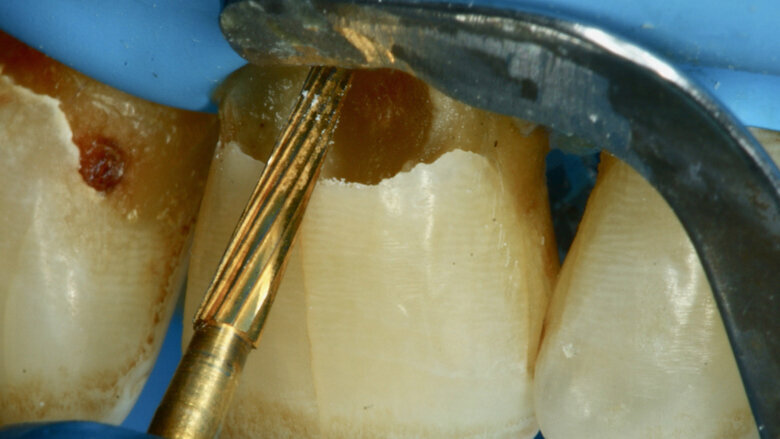

Paciente masculino de 65 años de edad se presenta al consultorio con lesiones de caries cavitadas en dentina activa (ICDAS 5) en dientes 11 y 21 (Figura 1). La lesión de la pieza 21 es extensa, mediante examen radiográfico y pruebas de vitalidad se diagnostica ausencia de compromiso pulpar. Como la lesión se extiende infra-gingivalmente, se opta por colocar dos hilos retractores 000 y 00 (Ultrapack, Ultradent, EE UU) y aislamiento absoluto con hilo dental tipo teflón y un clamp para anteriores (Figuras 2 y 3). Se inicia el procedimiento de remoción químico-mecánica utilizando un agente enzimático (Brix3000, Brix Medical Science, Argentina) durante 2 minutos (Figura 4). Utilizando curetas (Maillefer, EE UU) se elimina la dentina infectada (Figura 5) y el esmalte sin soporte dentinario (Figura 6) es eliminado con una fresa multilaminada (Figura 7) para mejorar el mimetismo y la adhesión al esmalte. Se complementa la instrumentación mecánica en el límite amelo-dentinario (Figuras 8 y 9).